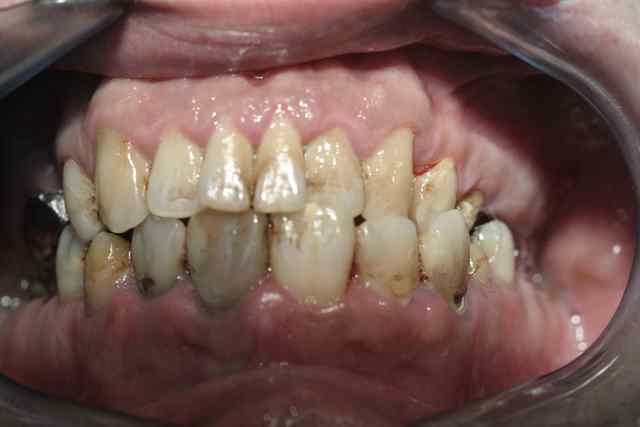

Mr x, fumeur ( 20c/Jour) vient me voir pour la deuxieme fois pour des douleurs parodontales tres violentes, qui ne cedent pas a l'ibuprofene et l'empeche de dormir. Or cette fois elles ne disparaissent pas avec la prescription d'antibiotique.

l'origine semble être au niveau de 11 12.

le diagnostic initial de GUN me parait éronné mais alors de quoi s'agit il?

age : 25

nombreux soins à realiser

hygiene mediocre

En tout cas vu la photo, les anciennes resto st completement iatrogènes, bcp de plaque et en plus fumeur.

Son problème de gingivite il est certain que ça provient de ses anciennes restaurations.